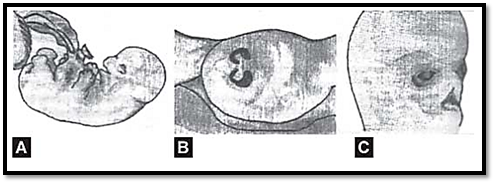

In a fetus as young as 10 weeks gestation, certain morphological abnormalities can be visualized, therefore the fetus should be examined for morphological abnormalities and a co-relation between gestational and developmental age should be made. For example, at 10 weeks gestation the presence of intestines in the umbilical cord is a normal finding (Fig. 1A). If the same condition is observed at a later gestational age, it is classified as omphalocele and could be associated with chromosomal defect like trisomy 18. Another example iscoloboma of the iris (Fig. 1B), which is a normal finding up to the age of 45 days, or cleft lip and palate, (Fig. 1C) which is normally seen up to 10 weeks of development. If these are seen after the above mentioned specific periods, these are labeled as developmental defects.

Figs 1A to C: (A) Physiological hernia in a fetus at 9 weeks, (B) Coloboma iris. (C) Cleft lip and palate at 10 weeks